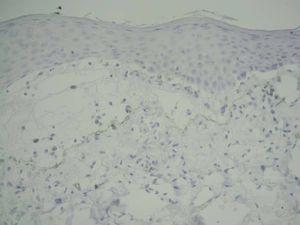

Se realizaron tres biopsias para estudio convencional: en una pápula de antebrazo, en una ampolla tensa y en un área cercana a la ampolla tensa. Asimismo se realizó una biopsia periampollosa para estudio con inmunofluorescencia directa.

La biopsia de la pápula de antebrazo (fig. 4) mostró una imagen típica de liquen plano, con hiperqueratosis ortoqueratósica, aumento de la capa granulosa, degeneración vacuolar de la capa basal, queratinocitos necróticos y un infiltrado dérmico en banda compuesto por linfocitos e histiocitos con presencia de melanófagos. No se vieron eosinófilos.

Fig. 4.—Biopsia de una pápula de antebrazo con hallazgos característicos de liquen plano.